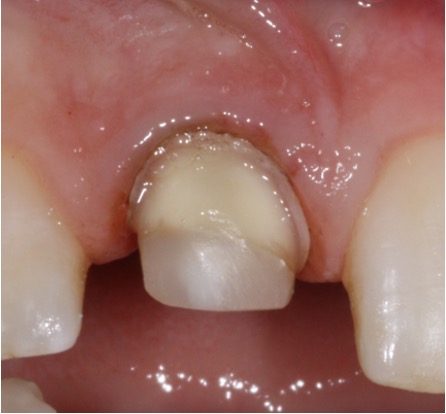

Secondary root canal treatment

Injury to the tooth can cause the root canal to shrink. High magnification and fine ultrasonic instruments are used to locate the root canal.

Fractured teeth

In this case a repeat root filling was completed. This is to minimise risk of infection from the exposed existing root filling. A fibre post and core was placed to build up the tooth sufficiently to retain a crown. This was then restored with an all ceramic crown. If there is insufficient tooth structure sometimes surgery can be carried out. In other cases it may not be possible to restore the tooth.